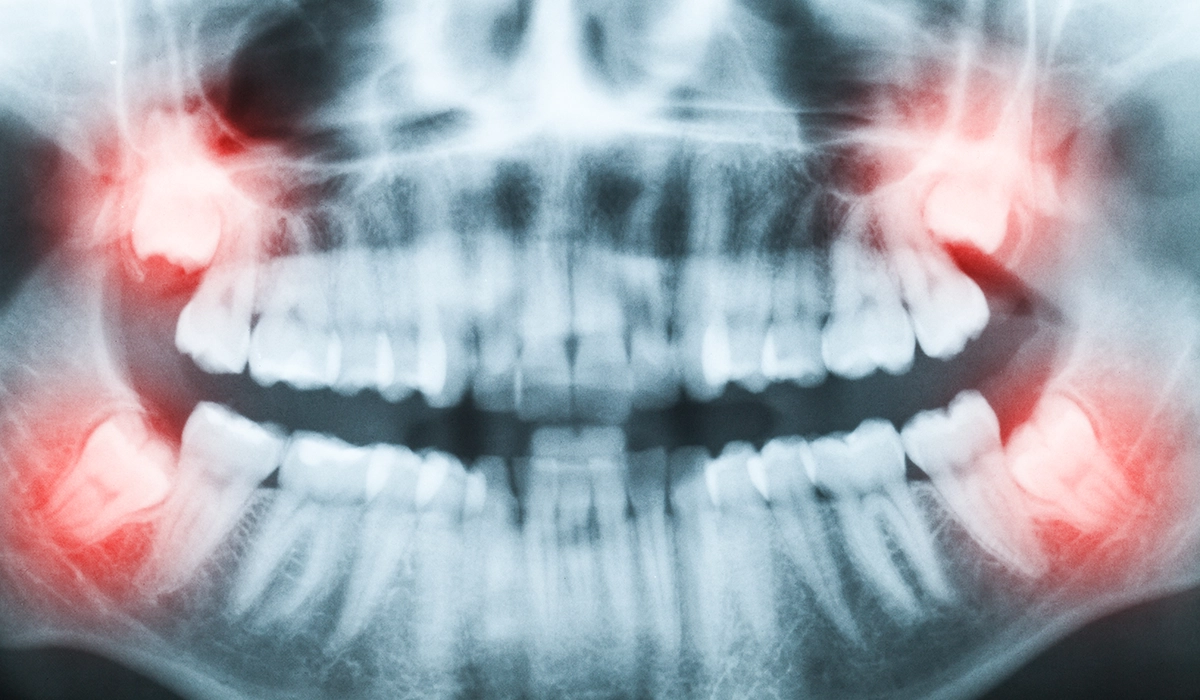

生え方で変わる抜歯の難易度

親知らずは真っ直ぐ生えてこないで横や斜めになって埋まっていることが多く、炎症のため腫れや痛みを起こしたり、虫歯となって抜歯をする必要があります。

そうなると、抜歯は困難で専門的な知識や技術が必要となります。

横向き・斜め向きの親知らずは

抜いたほうがベスト

親知らずの最大の問題は、他の永久歯のように真っ直ぐ生えてくることが少ないという点です。一番奥に位置する親知らずは生えるスペースが限られており、顎の骨が小さい人ほど生えづらくなります。歯は真っ直ぐに生え、上下でしっかり咬み合ってこそその機能を果たすことができます。

そのような意味において歯ぐきに埋まったままの親知らずや、横や斜めを向いた親知らずは本来の歯の機能が果たせないだけでなく、周囲に悪影響を及ぼしてしまいます。したがって正しい方向に生えていない親知らずは残しておいてもあまり意味がなく、かえってデメリットが多くなるため早めに抜いておいたほうがベストでしょう。